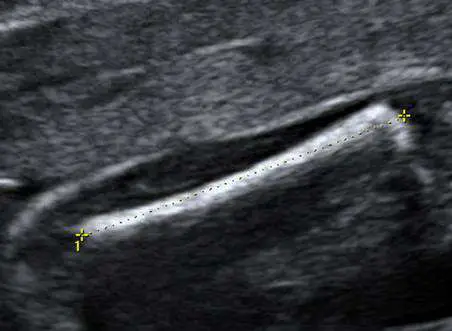

45 歲孕婦, G5P4 ,妊娠週數不明,接受產科超音波檢查,正在測量標的的名稱(雙十字之間)為何?

影像為二維產科超音波黑白灰階影像。畫面中可見一條細長、高回音(hyperechoic)、表面光滑的線形骨性結構,其特徵如下:

- 結構呈長條骨幹狀,兩端稍為膨大(股骨遠端及近端骨骺,為軟骨,回音較低,不計入測量範圍)

- 兩個黃色十字(雙十字)游標分別置於骨幹的兩端(近端大轉子至遠端股骨幹末端),以虛線相連,即為**FL(股骨長)**的測量標記

- 骨幹本身為高回音的細長白色線條,背後可見淡薄聲影(acoustic shadow),符合骨骼的超音波表現

- 無頭顱結構(排除 BPD/HC 測量)、無腹部橫切面(排除 AC 測量)、無頸後積液影像(排除 NT 測量)

此影像為測量胎兒股骨長度(FL)的標準切面,測量對象為已骨化的股骨骨幹(ossified femoral diaphysis),不包含軟骨部分。